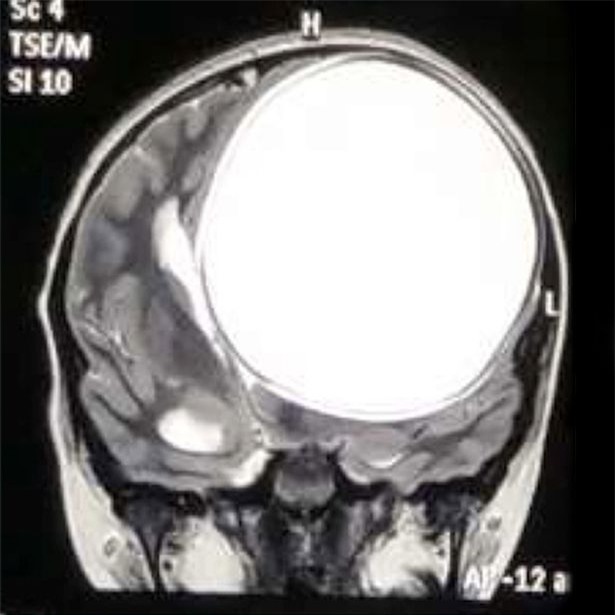

Hai tháng trước, cô bé được đưa tới gặp bác sỹ Chirag Solanki, một chuyên gia thần kinh và là bác sỹ phẫu thuật cột sống, tại bệnh viện Sterling ở Gujarat. Sau quá trình kiểm tra kỹ lưỡng và chụp cộng hưởng từ, họ phát hiện một nang sán khổng lồ trong não cô bé

Nang sán này nặng 675g và có kích thước 12,2x11x9,8 cm. "Tôi cho rằng bọc nang này đã phát triển trong đầu cô bé cách đây 8-10 năm. Càng phình to ra, nó càng gây ảnh hưởng nhiều và khiến cơn đau đầu ngày càng dữ dội”, bác sĩ nói.

“Nang sán này to bằng một nửa kích thước bộ não, trông như một quả bóng căng phồng và rất nguy hiểm bởi nó có thể vỡ bất cứ lúc nào, khiến cô bé tử vong ngay lập tức”. Bác sĩ Solanki nói gia đình cô bé rất sốc khi biết con gái mình mang một ổ nang sán lớn đến như vậy.